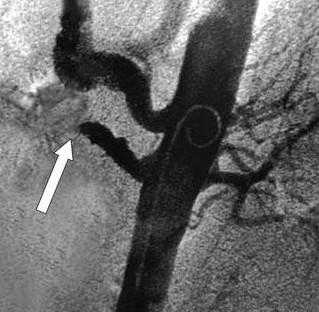

При обзорной рентгенографии брюшной полости определяется пневматизация кишечника, наличие горизонтальных уровней жидкости в брюшной полости. Специфическим методом диагностики острой окклюзии мезентериальных сосудов является селективная мезентерикография, которая уже на ранней стадии заболевания может выявить отсутствие кровотока в стволе и ветвях брыжеечной артерии. При наличии технической возможности выполняется магнитно-резонансная ангиография мезентериальных сосудов.

При подозрении на брюшную жабу обязательно выполняется ангиография мезентериальных сосудов (мезентерикография) или чревного ствола (целиакография), которая позволяет выявить окклюзию, стеноз, постстенотическое расширение артерий, локализацию и степень нарушения проходимости сосудов. При обзорной рентгенографии брюшной полости в ряде случаев удается обнаружить кальциноз брюшной аорты.

УЗИ брюшной аорты позволяет выявить тромбоз брыжеечной артерии или чревного ствола. Преимуществом метода является его быстрая доступность и отсутствие осложнений. Брюшная аорта осматривается в продольном и в поперечном срезе в режиме цветового картирования. Определяется скорость кровотока по аорте и ее ветвям. Метод обладает достаточно высокой чувствительностью, но его результаты зависят от опыта врача, проводящего исследование и правильной интерпретации полученных данных.

Рентгеновская ангиография

Метода введения контрастного вещества непосредственно в интересующие артерии. Проводится через доступ к артериям на руке или на ноге. Позволяет прицельно изучить проходимость брыжеечных артерий и одновременно выполнить вмешательство по восстановлению проходимости закупоренной артерии. Ренгтеноангиография выступает диагностическим и лечебным методом одновременно. С помощью специальных катетеров и инструментов возможно проведение рассасывания тромбов (тромболизиса) или его удаления - тромбэктомии.